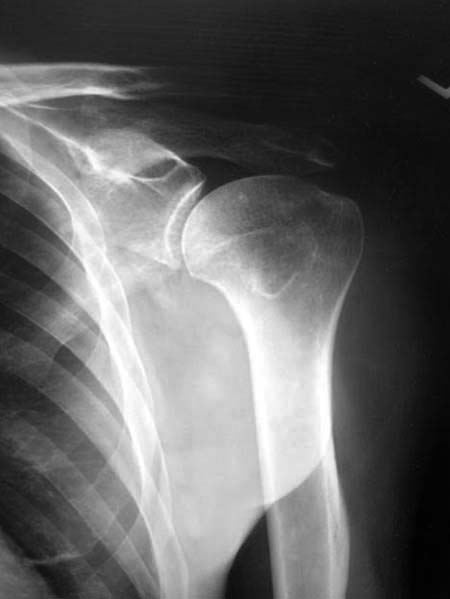

Данный перелом относится к перелому тело лопатки и несмотря на наслоение, где лопатка покрывает грудную клетку, но можно увидеть три большие фрагмента, которые находятся в разных плоскостях. Суставная поверхность расположена намного медиальнее, что нарушает бланс мышц, которая в последующем может привести к ограничению движения верхного пояса. Расположение суставной поверхности нуждается в уточнении дополнительными исследованиями, включая КТ и стандартные снимки плеча.!

Здесь пример, стандартные снимки: плечо и лопатка прямой снимок, аксиллярный и косой снимки (Y-view) и фиксация пластинами по краям, где имеется более твердая кость. Специальные пластины, хотя любая 2.7 или 3.5 мм тубулярная пластина подойдут для фиксации перелома. Риск операции - это повреждение нерва во время доступа и ре-фиксация ротаторной манжетки если потребуется широкий доступ!